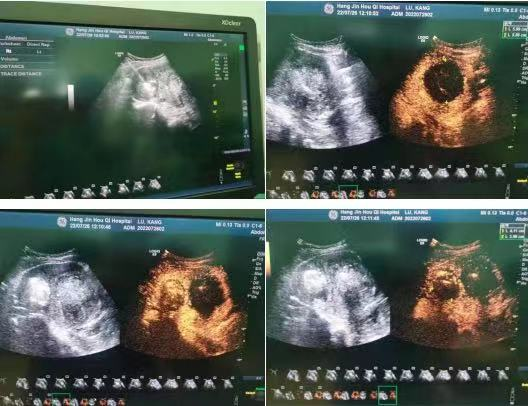

12月24日,杭锦后旗医院超声科在北京介入专家的指导下,成功开展超声引导下子宫肌瘤射频消融术1例、5例甲状腺结节消融术及1例肝包虫射频消融术。

肝包虫微波消融,将实性的囊壁、囊隔行移动式完全消融,通过术前术后超声造影、弹性成像结果比对,评价出患者体内的包虫完全灭活。手术利用微波消融术,创口小,体现出精准、微创、时间短和疗效佳的优势,减少了患者痛苦且不留疤痕,更具备不损伤正常肝功能的优点,有效防止了包虫囊液外溢引起患者过敏性休克的风险。术后患者恢复良好,无后遗症。

刘海芳主任介绍,微波消融治疗就是在彩超等影像方法引导下,将一根特制的微波针,经皮穿刺到病变中心区域。微波针尖部位有一个“微型微波炉”,释放的微磁场可使周围分子高速旋转运动并摩擦生温,使组织凝固,脱水坏死,从而达到治疗目的。这种方法定位准确,直接作用于病变细胞,疗效好,安全性高。今后,超声科将以精湛的技术,贴心的服务,先进的设备,更好的发挥科室优势,全力守好患者第一道健康防线。